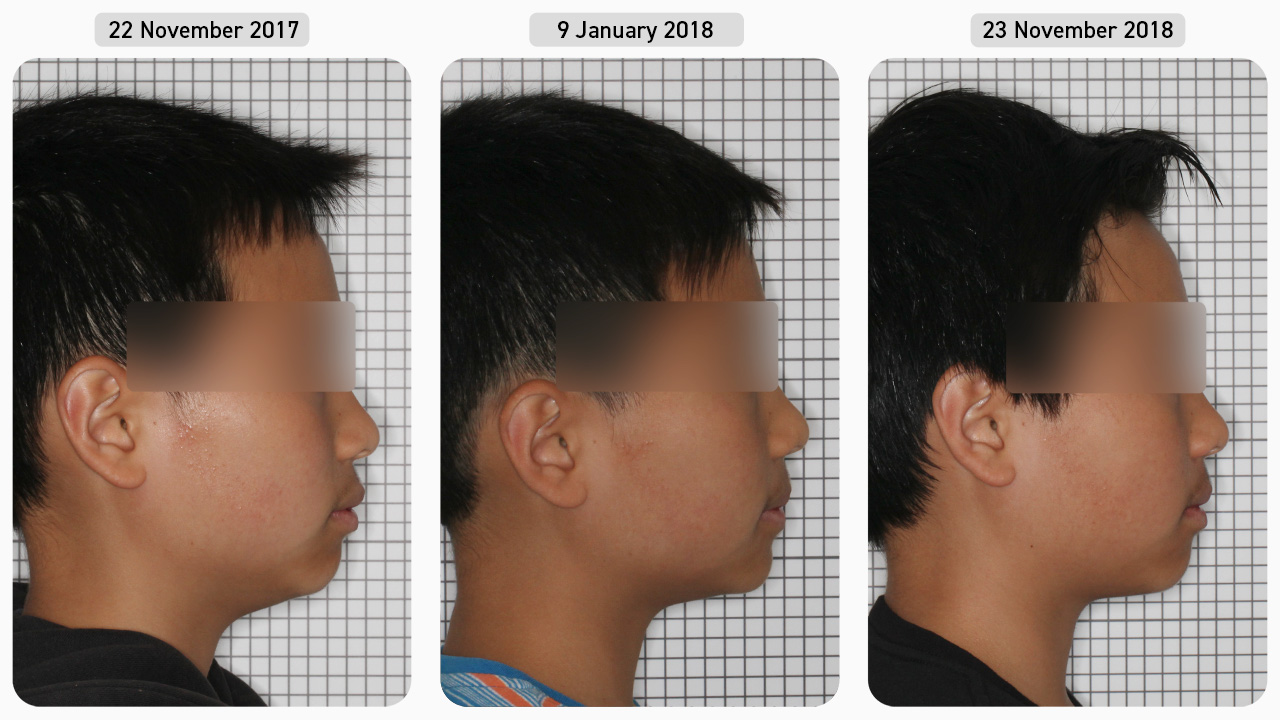

Case Study 4

This 13-year-old male patient presented with the chief complaint of protruding front teeth and an overjet. The patient has previously had treatment with an orthodontist who did upper arch expansion with a fixed expansion appliance. The patient wanted his protruding front teeth and overjet corrected, but he did not want fixed braces or anything that was visible in the mouth. After being presented with the various treatment options, the decision was made to undertake Myobrace® treatment, involving the use of a series of Myobrace® appliances and the Myobrace® Activities.

Pre-treatment

Using the Myofunctional Orthodontic Evaluation (MOE) form, we documented that this patient had a narrow upper arch (despite the previous arch expansion) with tipped in posterior teeth and proclined upper incisors. The mandible was retruded, with increased overbite and overjet, and mild dental crowding of the lower anterior teeth. His poor myofunctional habits included mouth breathing, low tongue posture and a reverse swallow. Since he was in the permanent dentition, he was treated with the Myobrace® for Teens series.

Dental Progression

Treatment began with the T1 appliance to establish nasal breathing and begin the correction of myofunctional habits. Two months later, his breathing function had improved, and he was consistently retaining the T1 overnight, so he progressed onto the T2 appliance which focuses on arch development and continued habit correction. You can already see the improvement in alignment of the lower anterior teeth and reduction in overjet after only two months of treatment. The patient remained on the T2 appliance for the majority of treatment while continuing to work through the Myobrace® Activities to correct his myofunctional habits. Notice the significant improvement in the upper arch form and reduced overbite and overjet. Once his myofunctional habits were largely corrected, the patient was issued the T4 appliance for retention.

Treatment Complete

After only one year of treatment, the goals of Myobrace® treatment have been achieved (establish nasal breathing, correct the poor myofunctional habits and attain good arch forms). Both the upper and lower arches are broad and round, the teeth are well aligned, and the increased overbite and overjet is resolved. At this point, the patient entered into the retention phase, which involved the use of the T4 appliance to retain the arch forms, alignment and correct habits so that he can continue to develop correctly.

Facial Progression

Now that the breathing and myofunctional disorders have been corrected, not only have the teeth and jaws aligned, but improvements can also be seen in the facial profile. The mandible has moved forward and the airway and posture have both improved. With good breathing and muscle function established, we expect the patient’s remaining development to continue in a favourable manner.